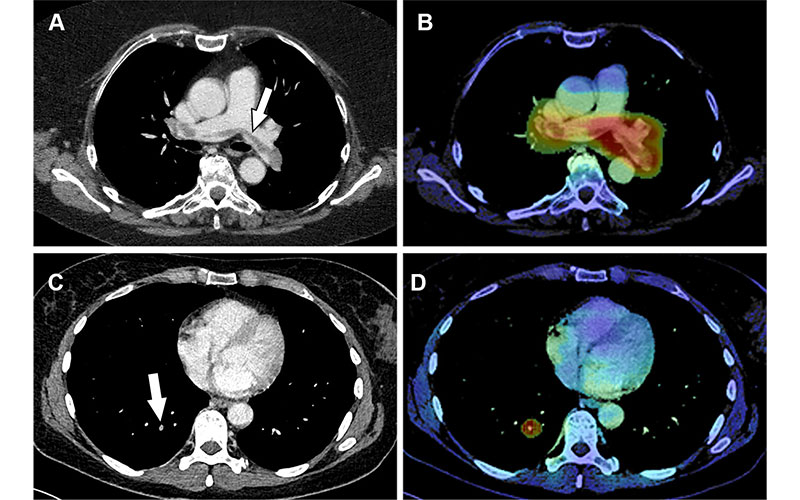

True-positive detection of incidental pulmonary embolism (PE) by the artificial intelligence (AI) software. (A, B) Images in a 68-year-old woman who underwent routine CT with intravenous contrast agent for outpatient follow-up of melanoma. (A) Axial CT image shows a large filling defect straddling the bifurcation of the pulmonary trunk (arrow) and extending into both pulmonary arteries, compatible with an incidental saddle PE. (B) Corresponding AI heatmap highlights the detected abnormality (red), thereby prioritizing the case in the radiologists’ worklist. (C, D) Images in a 58-year-old woman with a history of rectal cancer undergoing outpatient follow-up. (C) Axial restaging CT image with intravenous contrast agent shows a small incidental subsegmental PE in the right lower lung lobe (arrow). (D) Corresponding AI heatmap enables the radiologist to localize the finding (red).